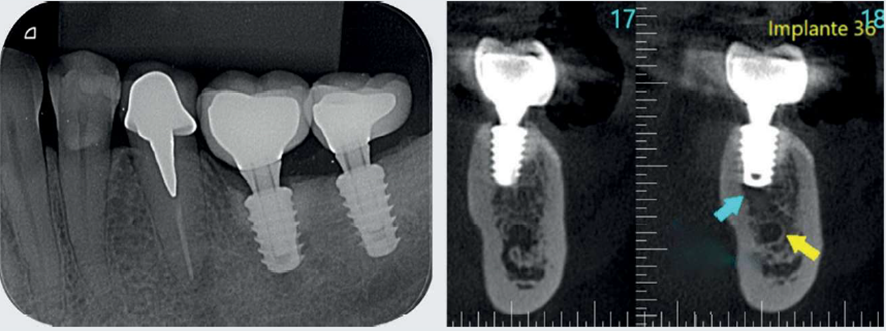

Após mais de 18 meses de proservação, observou-se um excelente resultado no controle da infecção peri-implantar e na regeneração do defeito ósseo (Figura 7). Com quatro anos de controle pós-tratamento, na avaliação clínica e nas imagens da proservação radiográfica e tomográfica, foi possível observar aspectos de estabilidade no tecido ósseo regenerado e compatíveis com a saúde dos tecidos peri-implantares (Figuras 8 e 9).